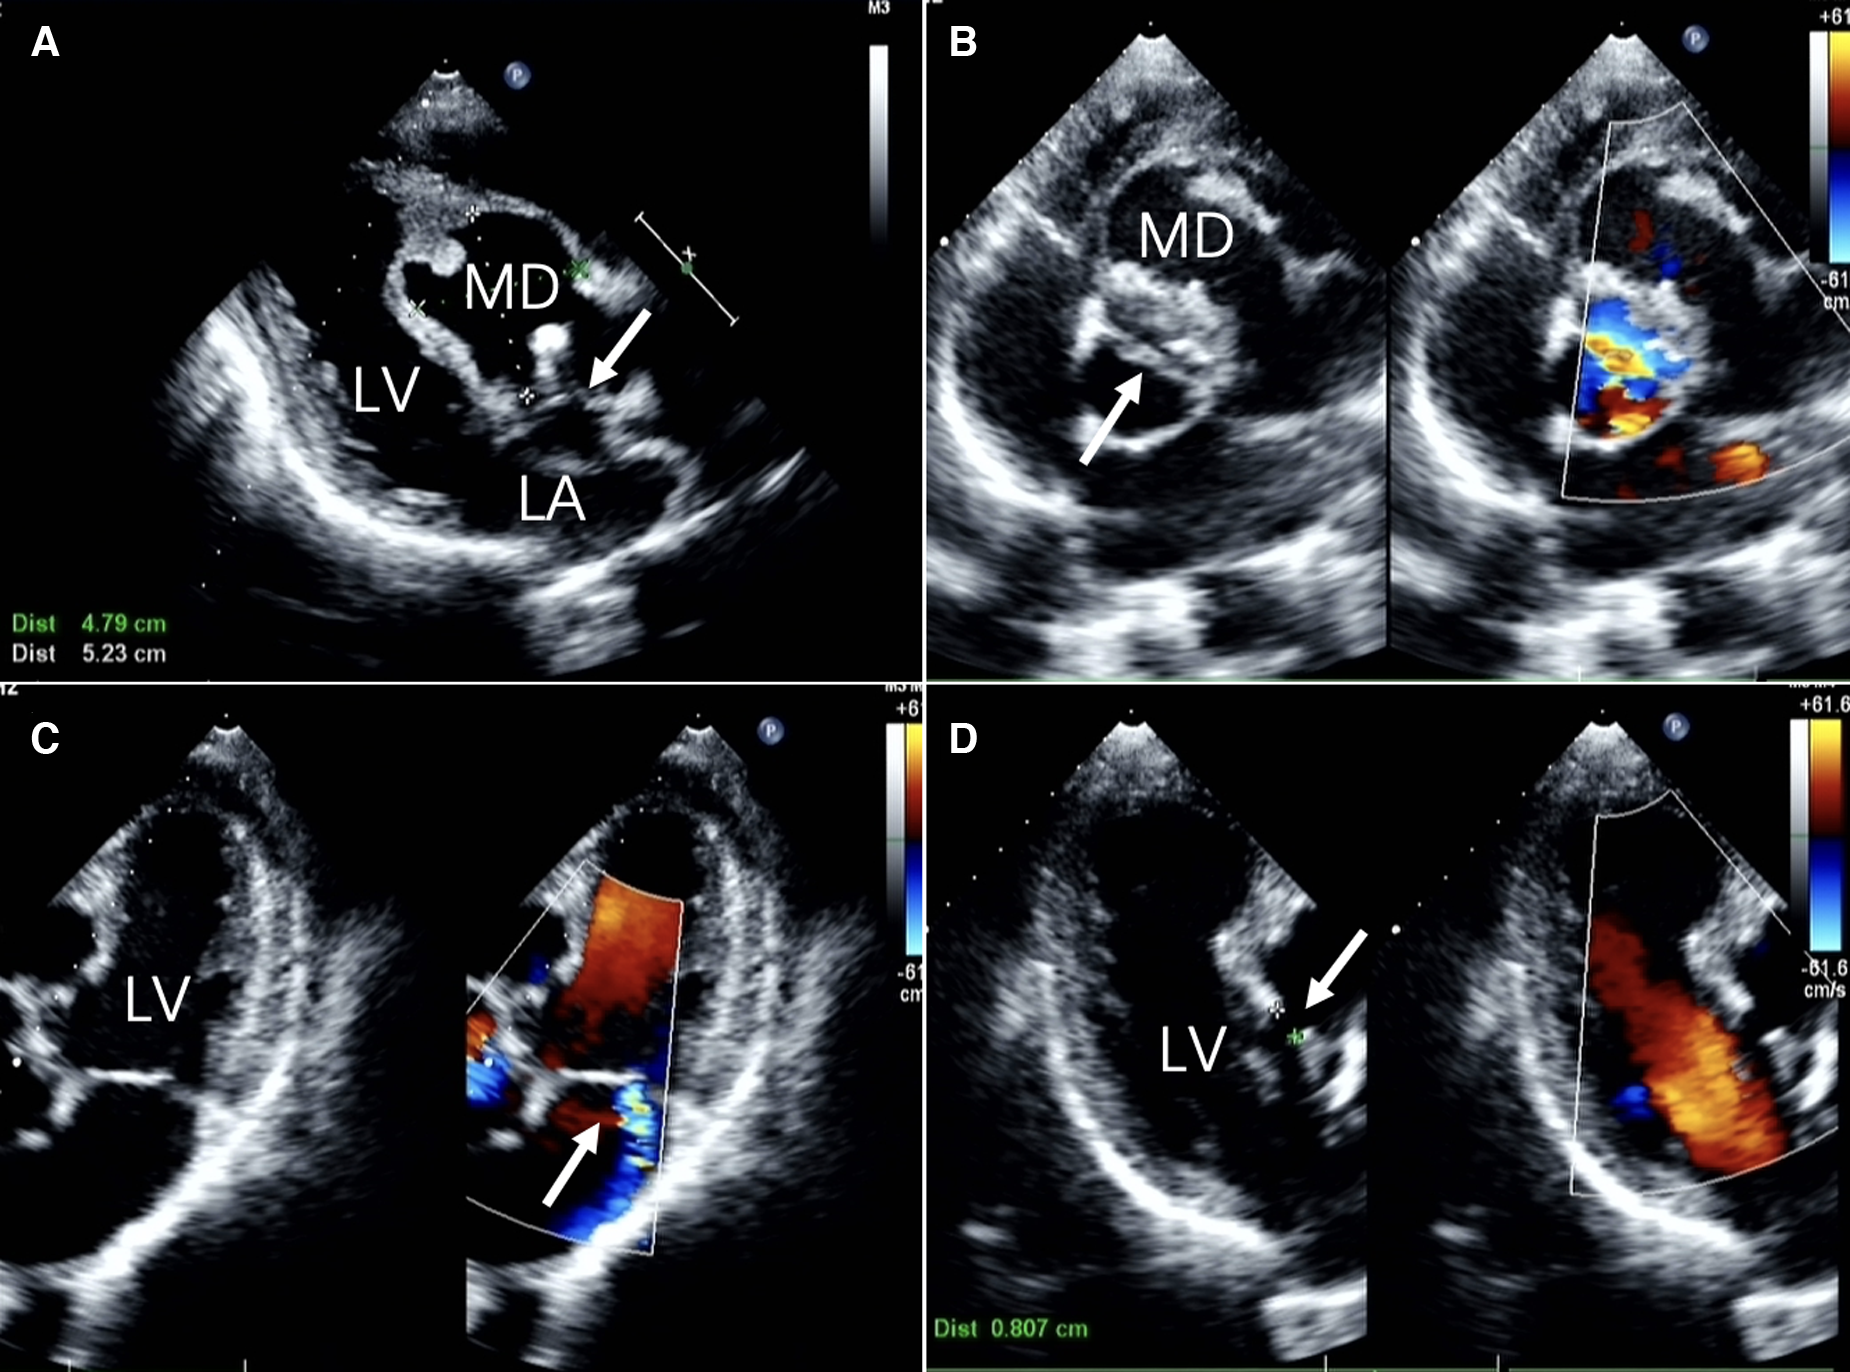

Figure 1

Two-dimensional transthoracic echocardiographic images (A) long-axis view of the left ventricle showing echo interruption, no echo in the interventricular septum.(white arrow) (B) the short-axis cross-sectional view of the aorta demonstrates a bicuspid aortic valve anomaly. (white arrow) (C) the non-standard pentachamber cardiac section reveals mitral valve eccentric regurgitation. (D) The three-chamber cardiac cross-section reveals the dimension of the orifice. LA, left atrium; LV, left ventricle; MD, Myocardial dissection.

A 60-year-old Chinese male presented with upper abdominal pain accompanied by dizziness and palpitations for 2 days. The patient's heart function was classified as NYHA functional class IV, and vital signs and blood biochemistry tests showed no critical indicators. Transthoracic echocardiography (TTE) revealed a myocardial dissection with a pouch-like protrusion into the right ventricle, interrupted wall echo in the septum and the basal segment of the left ventricular anterior wall, with an adherent hyperechoic structure within (Figure 1). A dual-source CT scan shows the diameter of the ascending aorta to be approximately 4.8 cm. There was a BAV and fusion of the left and right aortic sinuses, with an outward protrusion forming a cavity in the anterior aortic sinus. Myocardial dissection formation, likely due to rupture of the anterior aortic sinus, was suspected. The neck of the aneurysm had a diameter of approximately 1.4 cm, and the morphology of the aneurysm was irregular, with localized pushing on the left coronary artery (Figure 2).

In general, echocardiography demonstrates exceptional sensitivity to both vascular walls and myocardium. Within the ultrasound examination, our patient's presentation was characterized by an aortic sinus that protruded into the right ventricle, displaying an interrupted wall echo. Notably, there is an anomalous echo-free region in the basal segment of the interventricular septum and the left ventricular anterior wall. This manifestation signifies the rupture of the sinus aneurysm, resulting in the tearing of the corresponding interventricular septum and myocardium.